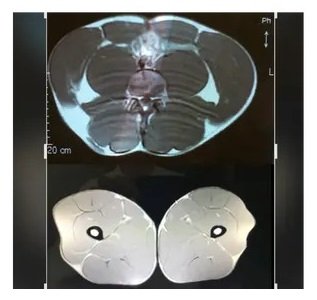

4. Fat in Your Muscles Cause Inflammation & is Present in Proportion to Visceral Fat

Want to know why you become weak as you age and your legs and arms start wobbling when elderly? Take a look here then: This image shows a large amount of abdominal visceral fat in a 63-year-old client on top and an MRI scan through his legs showing white streaks which are fatty infiltrates degrading both the health and performance of muscles when present. They correspond to the amount of visceral fat. Sadly, neither visceral fat nor fatty infiltrates are EVER read, commented on or addressed by the medical system. You are just allowed to worsen making the system more money through more needed drugs.. Get both your Visceral Fat & Muscle Fat measured today and start eliminating chronic disease. You have to look out for yourself if you really want to get better and stop worsening.